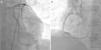

Case reportA man in his 40s was admitted to our department for recurrent chest pain, cough and expectoration during the previous three days. The patient had no relevant previous history. The admission electrocardiogram (ECG) showed 1–2 mm ST-segment elevation and QS waves in leads II, III and aVF (Figure 1A); the myocardial injury marker troponin I was elevated to 13.02 ng/ml. The patient was initially diagnosed with suspected acute inferior STEMI. However, seven hours after admission, he complained of severe chest pain, dyspnea and sweating. Immediate blood pressure determination was 54/33 mmHg and immediate 12-lead ECG showed 4–5 mm ST-segment elevation in leads II, III and aVF, exhibiting dynamic changes from the admission ECG (Figure 1B). A diagnosis of acute inferior STEMI was established. Blood pressure was maintained at normal levels by dopamine. An urgent coronary angiography was also performed. However, all the major coronary arteries were demonstrated to be normal except for a myocardial bridge in the left anterior descending artery (Figure 2). The diagnosis was subsequently corrected to fulminant myocarditis. Two hours after angiography, the patient experienced cardiogenic shock again, and his blood pressure fell to 67/35 mmHg, resistant to cardiotonic or vasopressor drugs, including dopamine, dobutamine and aramine. The shock was not effectively reversed until emergent IABP implantation. Four hours after IABP implantation, the patient suffered Adams-Stokes syndrome three times; the ECG monitor showed that one attack was due to ventricular tachycardia (Figure 3A), while the other two were due to ventricular fibrillation (Figure 3B). Synchronized cardioversion was performed three times with an energy setting of 200 J. The patient was successfully resuscitated and continuous amiodarone was administered. However, about 10 hours later, he again suffered a syncopal episode, with blood pressure of 72/37 mmHg. The ECG monitor recorded high-degree atrioventricular block (AVB), with a longest R-R interval of 7.0 s (Figure 3C). A temporary pacemaker was emergently implanted and the bradycardia was effectively resolved (Figure 3D). A dose of 450 mg hydrocortisone was subsequently administered and maintained continuously for one week.

DiscussionWe report a case of severe fulminant myocarditis and share our experience in diagnosing and treating this patient. Several points deserve consideration. Firstly, this case was initially misdiagnosed as acute inferior STEMI. In clinical practice, it is unusual for myocarditis to manifest with a STEMI-like ECG.10 However, in this case, the ECG demonstrated features seen in myocardial infarction as well as dynamic changes typical of STEMI. Under such circumstances, coronary angiography is still the most reliable approach for differential diagnosis. We performed emergency angiography and effectively differentiated the patient's condition from STEMI. The results of IgG serology and coronary CT angiography further supported the diagnosis of myocarditis.